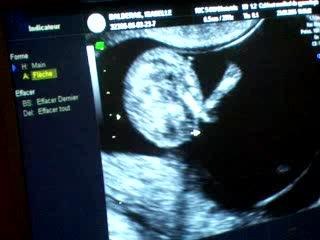

Echographie -- L'Embryon De 5 A 9 Semaines

Pour en savoir plus, consultez le site officiel du Dr. Safia Taieb Gynécologue Obstétricienne à Monastir - Tunisie br br br L'échographie du premier trimestre constitue un moment privilégié pour la maman, son premier contact avec le bébé avant même de le sentir bouger dans son ventre...